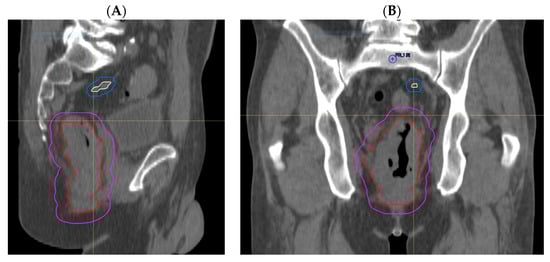

3.1.2. Comparison of Volumes Using Adjusted MRI Reporting with Historical Radiotherapy Volumes